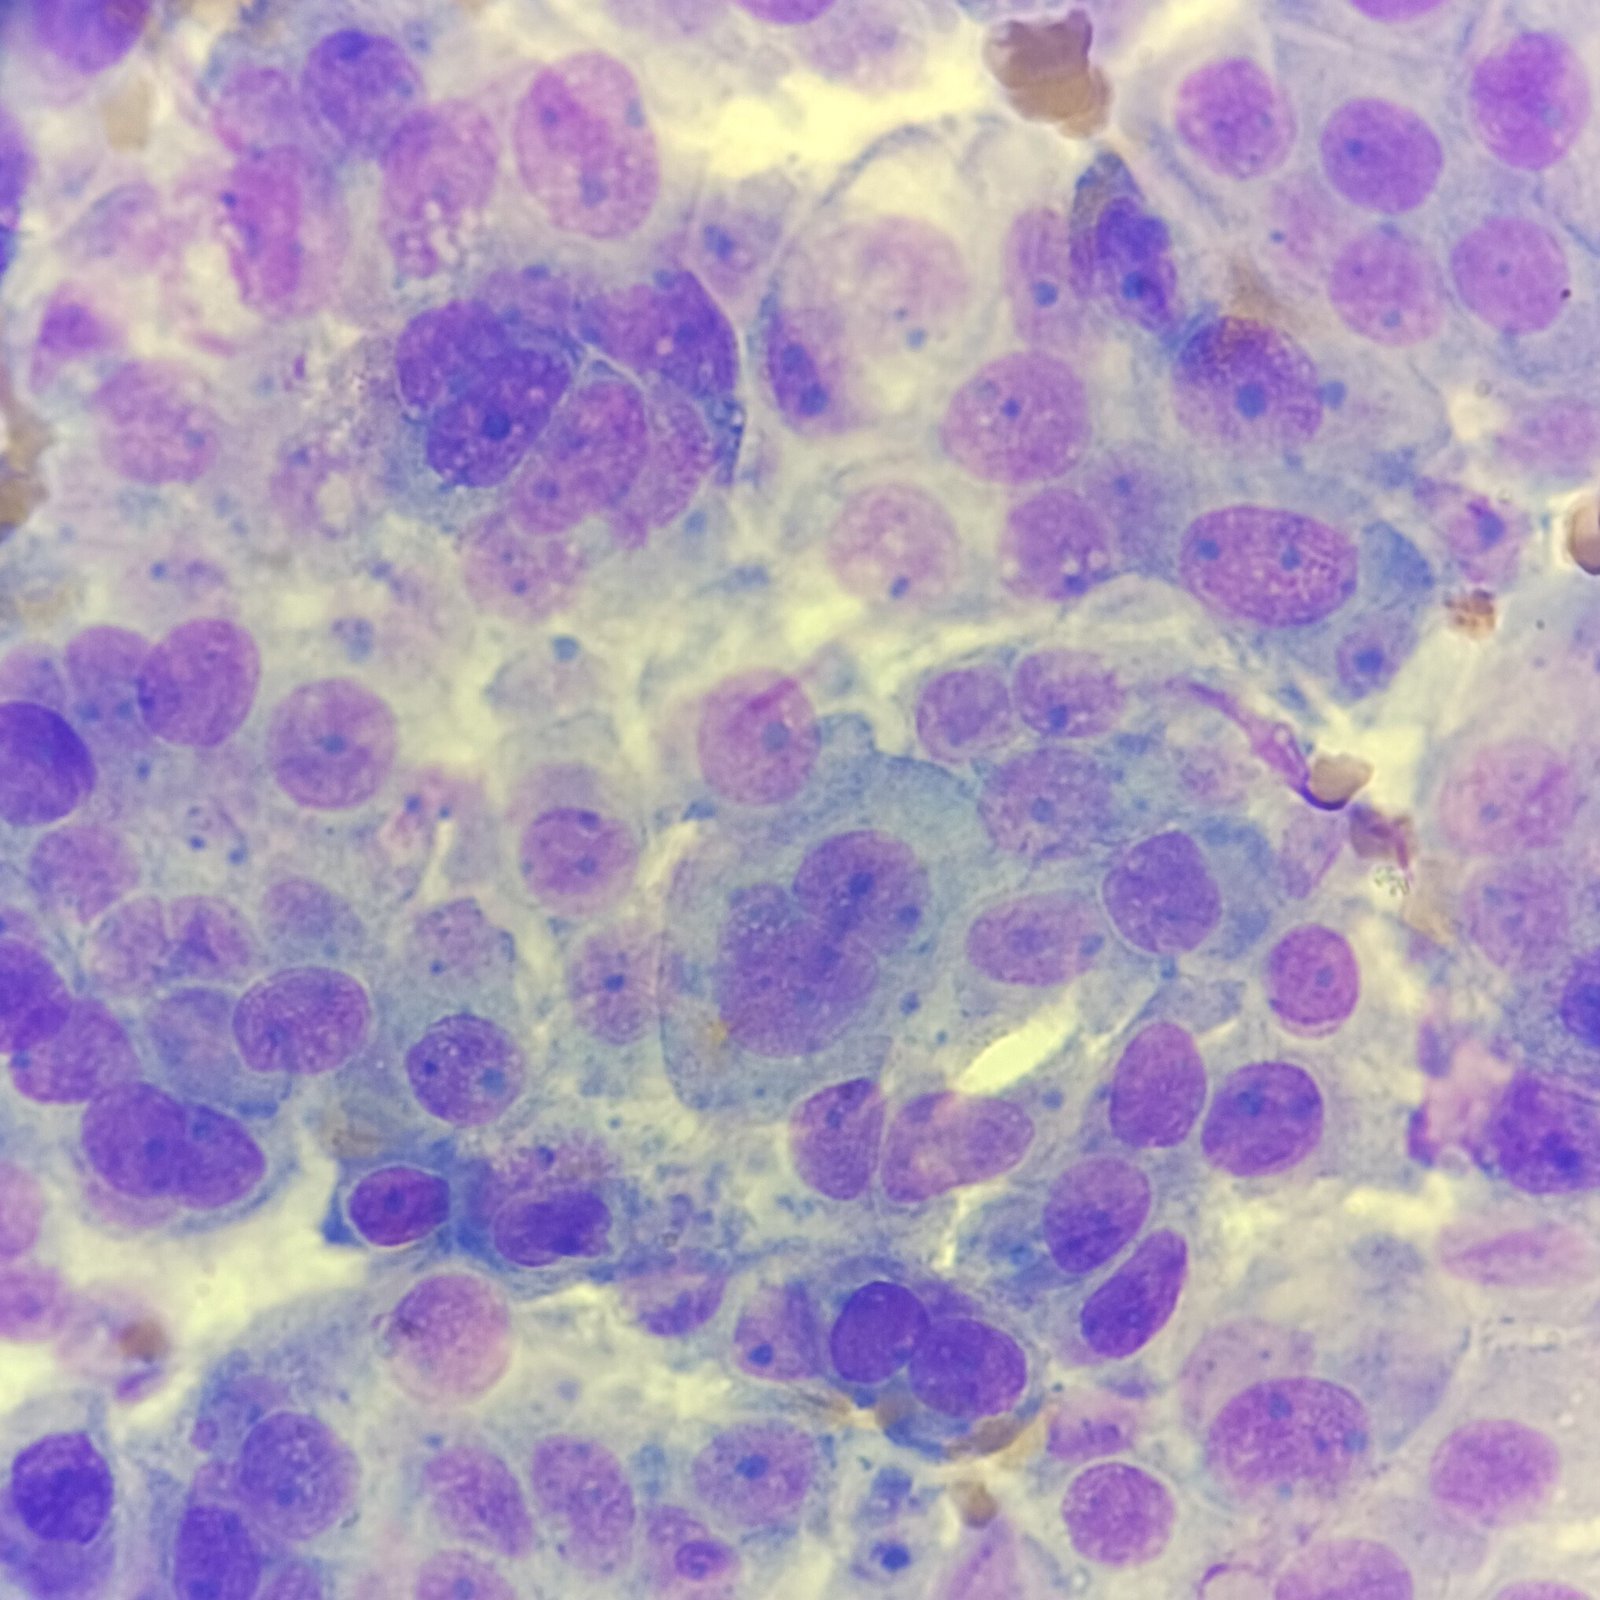

Macrophages are about the same size as mesothelial cells, so the two can often be confused. Macrophages can usually be differentiated by the presence of vacuoles and a lacey chromatin. If both cell types are present and differentiation is difficult, take a look around the slide to get an idea of each kind of morphology before starting a differential.

Both malignant cells and mesothelial cells can clump together. However, malignant cells will not have the windows between cells.